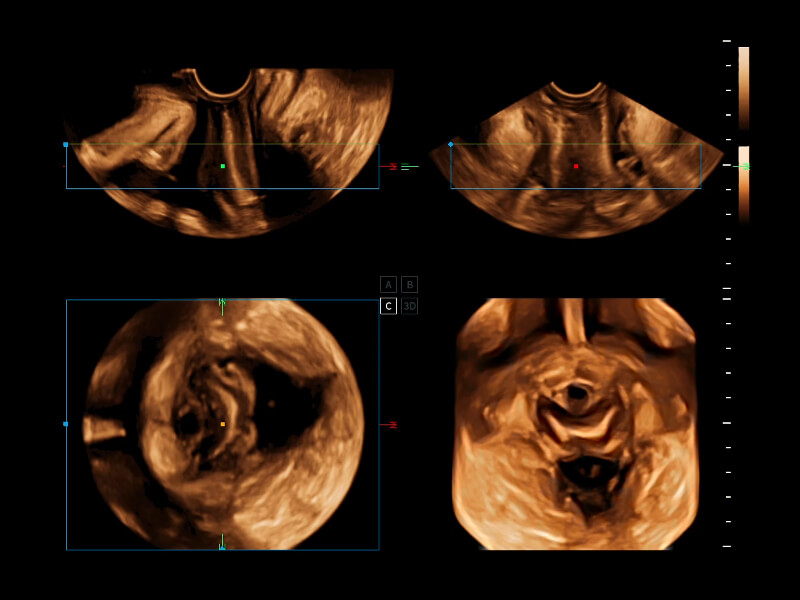

作为开立医疗全新打造的超高端旗舰超声产品,从探头抬起唤醒开启扫查到多维探头发射接收,通过先进的场成像发射、自适应聚合重建等技术,基于RF Data原始射频数据在图像生成、高端功能等方面实现突破,为妇产科、儿科提供全方位临床解决方案。

梦溪®P80以“关爱女性”为基石,提供全方位的解决方案,量身定制以满足女性的健康需求,涵盖妇科、生殖健康检查、产前筛查及产后康复等领域。

通过工作流协议、远程访问、自动探头激活和人体工程学优化设计等功能,旨在提高临床工作效率